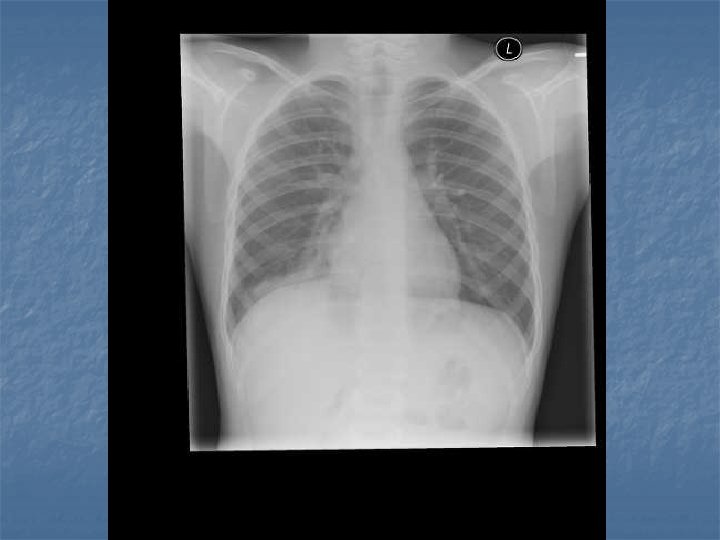

CXR Findings VIRAL n Peribronchial thickening n Diffuse interstitial infiltrates n Hyperinflation BACTERIAL n Subsegmental, segmental or lobar infiltrates n Air bronchograms n Round pneumonia in early S. pneumo n n M. pneumo diffuse infiltrates out of proportion to clinical findings (or bronchopneumonia infiltrates in lower lobes) Bilateral reticulonodular interstitial infitrates

n n n 50% bacterial pneumonia will have lobar infiltrate Can also see alveolar infiltrates Round pneumonia seen with S. pneumo

CXR Summary n In combination with physical exam, do a CXR when: Questionable dx n Admitting pt n <3 y with fever >39 C and WBC >15 n Complicated pneumonia suspected n

Immunocompromised/Elderly n n Atypical presentation (insidious onset or may be confused with CHR or respiratory compromise from lung dz) Atypical organisms/opportunistic infections may be subtle

Nursing Home Acquired Pneumonia n n Prevalence 1. 1 -2. 5% in chronic care facilities, incidence 13 - 48% In Calgary single most common reason for T/F to hospital (18. 5% of all admissions) Mortality as high as 44% Exclusions: aspiration pneumonia, hospital acquired, CF, bronchiectasis, TB